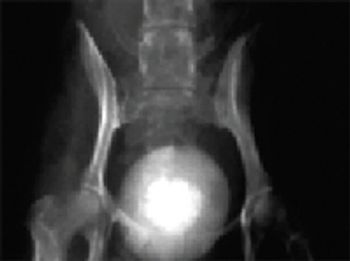

Knowledge of urolith composition is important because contemporary methods of detection, treatment and prevention of the underlying causes of urolithiasis are primarily related to knowledge of urolith composition. The following discussion is based on quantitative analysis of 275,000 canine uroliths submitted to the Minnesota Urolith Center from 1981 to the spring of 2006. (For additional details related to feline uroliths and feline urethral plugs, refer to the Diagnote entitled "Changing trends in composition of feline uroliths and feline urethral plugs," published in the April 2006 issue of DVM Newsmagazine (Vol. 37, No.4).